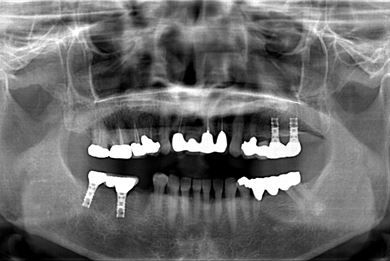

インプラントの症例写真 IMPLANT

骨再生スピードインプラント治療+セラミック治療

| 治療方針 | 骨再生法によりインプラント治療を可能にする。抜歯と同時にインプラント埋入を行い、治療期間を短縮する。 | ||||||||||||||||||||||||||||||||

| 治療内容 | インプラント3本(抜歯即日スピードインプラント、GBR)、メタルボンドセラミッククラウン4本 | ||||||||||||||||||||||||||||||||

| 総治療費 | 1,509,902円 | ||||||||||||||||||||||||||||||||

| 治療期間 | 1年5ヶ月 |